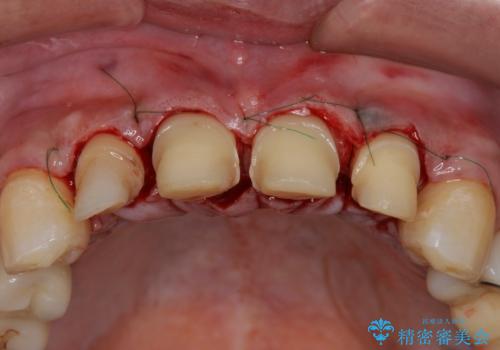

虫歯のマイクロスコープによる丁寧な除去、根管治療、深い虫歯に対する挺出(エクストリュージョン)および歯周外科を行ったのち精度の高いセラミッククラウン製作治療を計画します。

虫歯の放置により、根管治療や深い虫歯に対する処置が必要になりましたが丁寧に一つづつ処置を行ったことで抜歯をすることなく歯を残すことができました。

セラミッククラウンの製作をする前に、歯内・歯周環境の整備は非常に大切です。